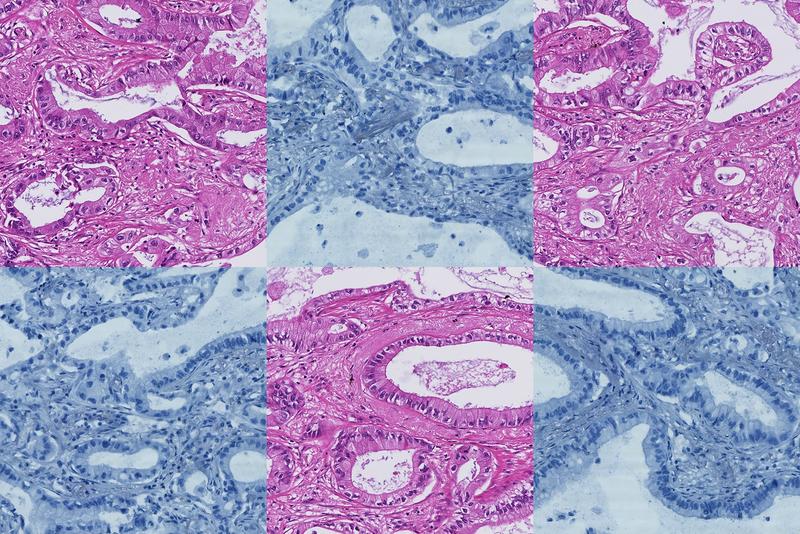

Die Zahl der Krebserkrankungen steigt laut Weltgesundheitsorganisation (WHO) weltweit signifikant an. Zentral für eine sichere Diagnose und erfolgreiche Therapie sind eindeutige Indikatoren, auch Biomarker genannt. Lernfähige KI-Systeme tragen dazu bei, solche messbaren Parameter in pathologischen Bildern aufzuspüren. Forschenden des Fraunhofer-Instituts für Digitale Medizin MEVIS ist es in Zusammenarbeit mit der RWTH Aachen, der Universität Regensburg und der Hannover Medical School gelungen, hierfür ein Basismodell zu entwickeln, das Gewebeproben anhand eines Bruchteils der üblichen Trainingsdatensätze schnell, zuverlässig und ressourceneffizient analysiert.

Analog dazu erlernt ihr KI-Modell in seiner Grundausbildung aus einer breiten Sammlung von Gewebeschnittbildern mit verschiedenen Fragestellungen allgemeine Merkmale und Gesetzmäßigkeiten, sogenannte Tissue Concepts. In der Kombination dieser Aufgabenstellungen entstehen die großen Datenmengen, die für das Training eines robusten KI-Basismodells benötigt werden. In einem zweiten Schritt werden die gelernten Konzepte für eine spezifische Fragestellung genutzt. Auf diese Weise können die Algorithmen mit deutlich weniger Daten Biomarker identifizieren, die etwa verschiedene Tumorarten unterscheiden.

Zudem nutzt das Team das am Institut entwickelte Bildregistrierungsverfahren HistokatFusion. Es bietet die Möglichkeit, automatisch annotierte Trainingsdaten etwa aus immunhistochemischen Gewebefärbungen zu generieren, die Proteine oder andere Strukturen mit Hilfe von markierten Antikörpern sichtbar machen. Dazu kombiniert es Informationen aus mehreren histopathologischen Bildern. Diese automatisch erzeugten Markierungen bauen die Fachleute in das Training ihres Modells ein und beschleunigen so die Sammlung von annotierten Trainingsdaten.